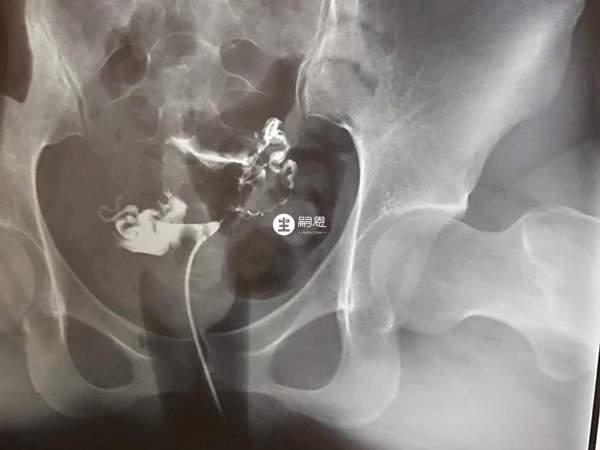

我28歲,老公30歲,我老公最近婚檢查出精子質量不好,數量少活力低,我們備孕半年了還沒懷上,性生活正常,醫生是建議我們去做人工授精的,但是我去網上看說人工授精的成功率是非常低的,想問問一般女性需要具備什麼身體條件做人工授精才能成功懷孕?做人工授精要求女方輸卵管必須要有一側或雙側通暢才行,如果輸卵管堵塞那麼精卵就無法見面結合。同時要求女性月經週期正常有正常的排卵,不存在慢性生殖道炎症,子宮環境較好,內膜厚度在8mm以上,無傳染病或遺傳性疾病才行,如果不滿足這些身體條件,女方做人工授精是很難成功懷孕的。